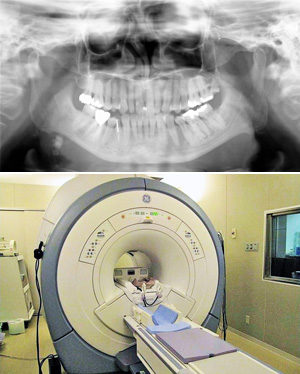

歯科放射線科

パノラマエックス線写真(上)

MRI (Magnetic Resonance Imaging) :磁気共鳴画像装置(下)